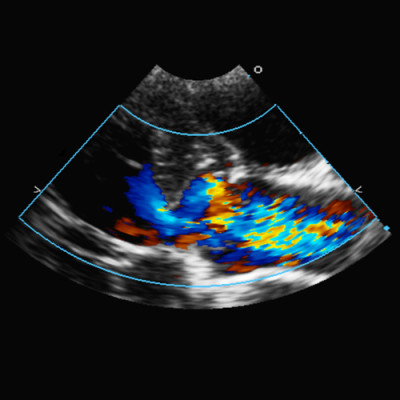

Specijalističke veterinarske ambulante Marković ovlaštene su od strane Hrvatskog kinološkog saveza za izdavanje certifikata o zdravstvenom stanju pasa i to za oftalmološki, kardiološki i test za gluhoću.